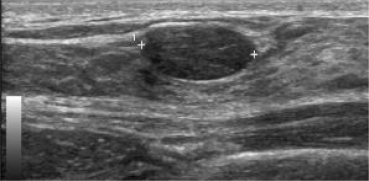

Figuur 2

Echografische afbeelding van een irregulaire onscherp begrensde massa links lateraal van de tepel. Op basis van de vorm en begrenzing moet deze massa worden verslagen als verdacht voor maligniteit, BI-RADS 4 (pathologie: invasief ductaal carcinoom).